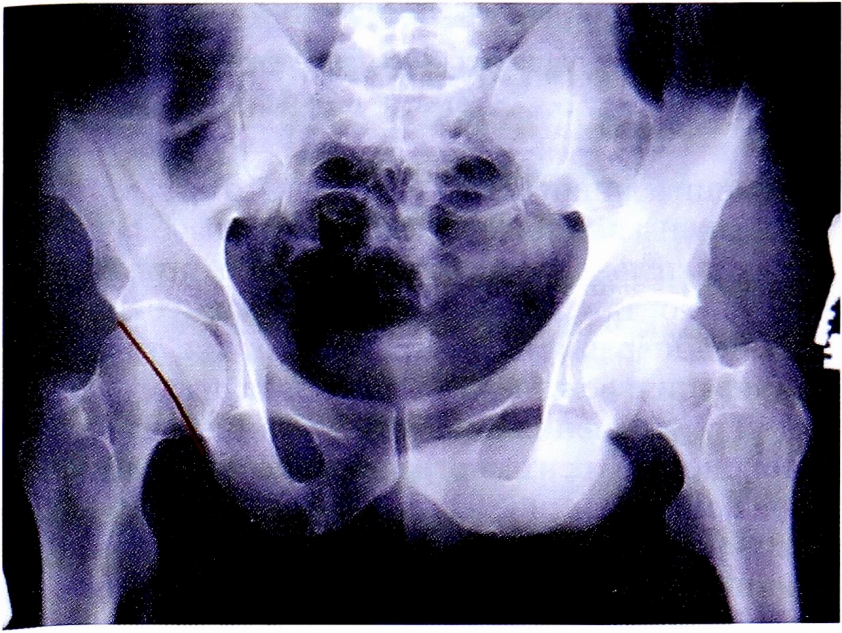

На обзорной рентгенограмме, представленной на рис. 14 достоверно определяется нарушение непрерывности подвздошно-гребешковой и подвздошно-седалищной линии.

Рис. 14. Обзорная рентгенография таза пациента с переломом вертлужной впадины.

Fig. 14. АР pelvic X-ray of patient with acetabular fracture.

С помощью рентгенограммы в косой запирательной проекции, выполненной по методике НМИЦ ТО, диагностирован перелом задней стенки со смещением отдельного фрагмента. Также с помощью прицельного снимка определена целостность контуров запирательного отверстия (рис. 15).

Рис. 15. Рентгенография правого тазобедренного сустава в косой-запирательной проекции, выполнена по методике НМИЦ ТО. Стрелками показан перелом и отдельный фрагмент задней стенки.

Fig. 15. Obturator oblique view made with CITO method. Arrows shows separated posterior wall fragment.